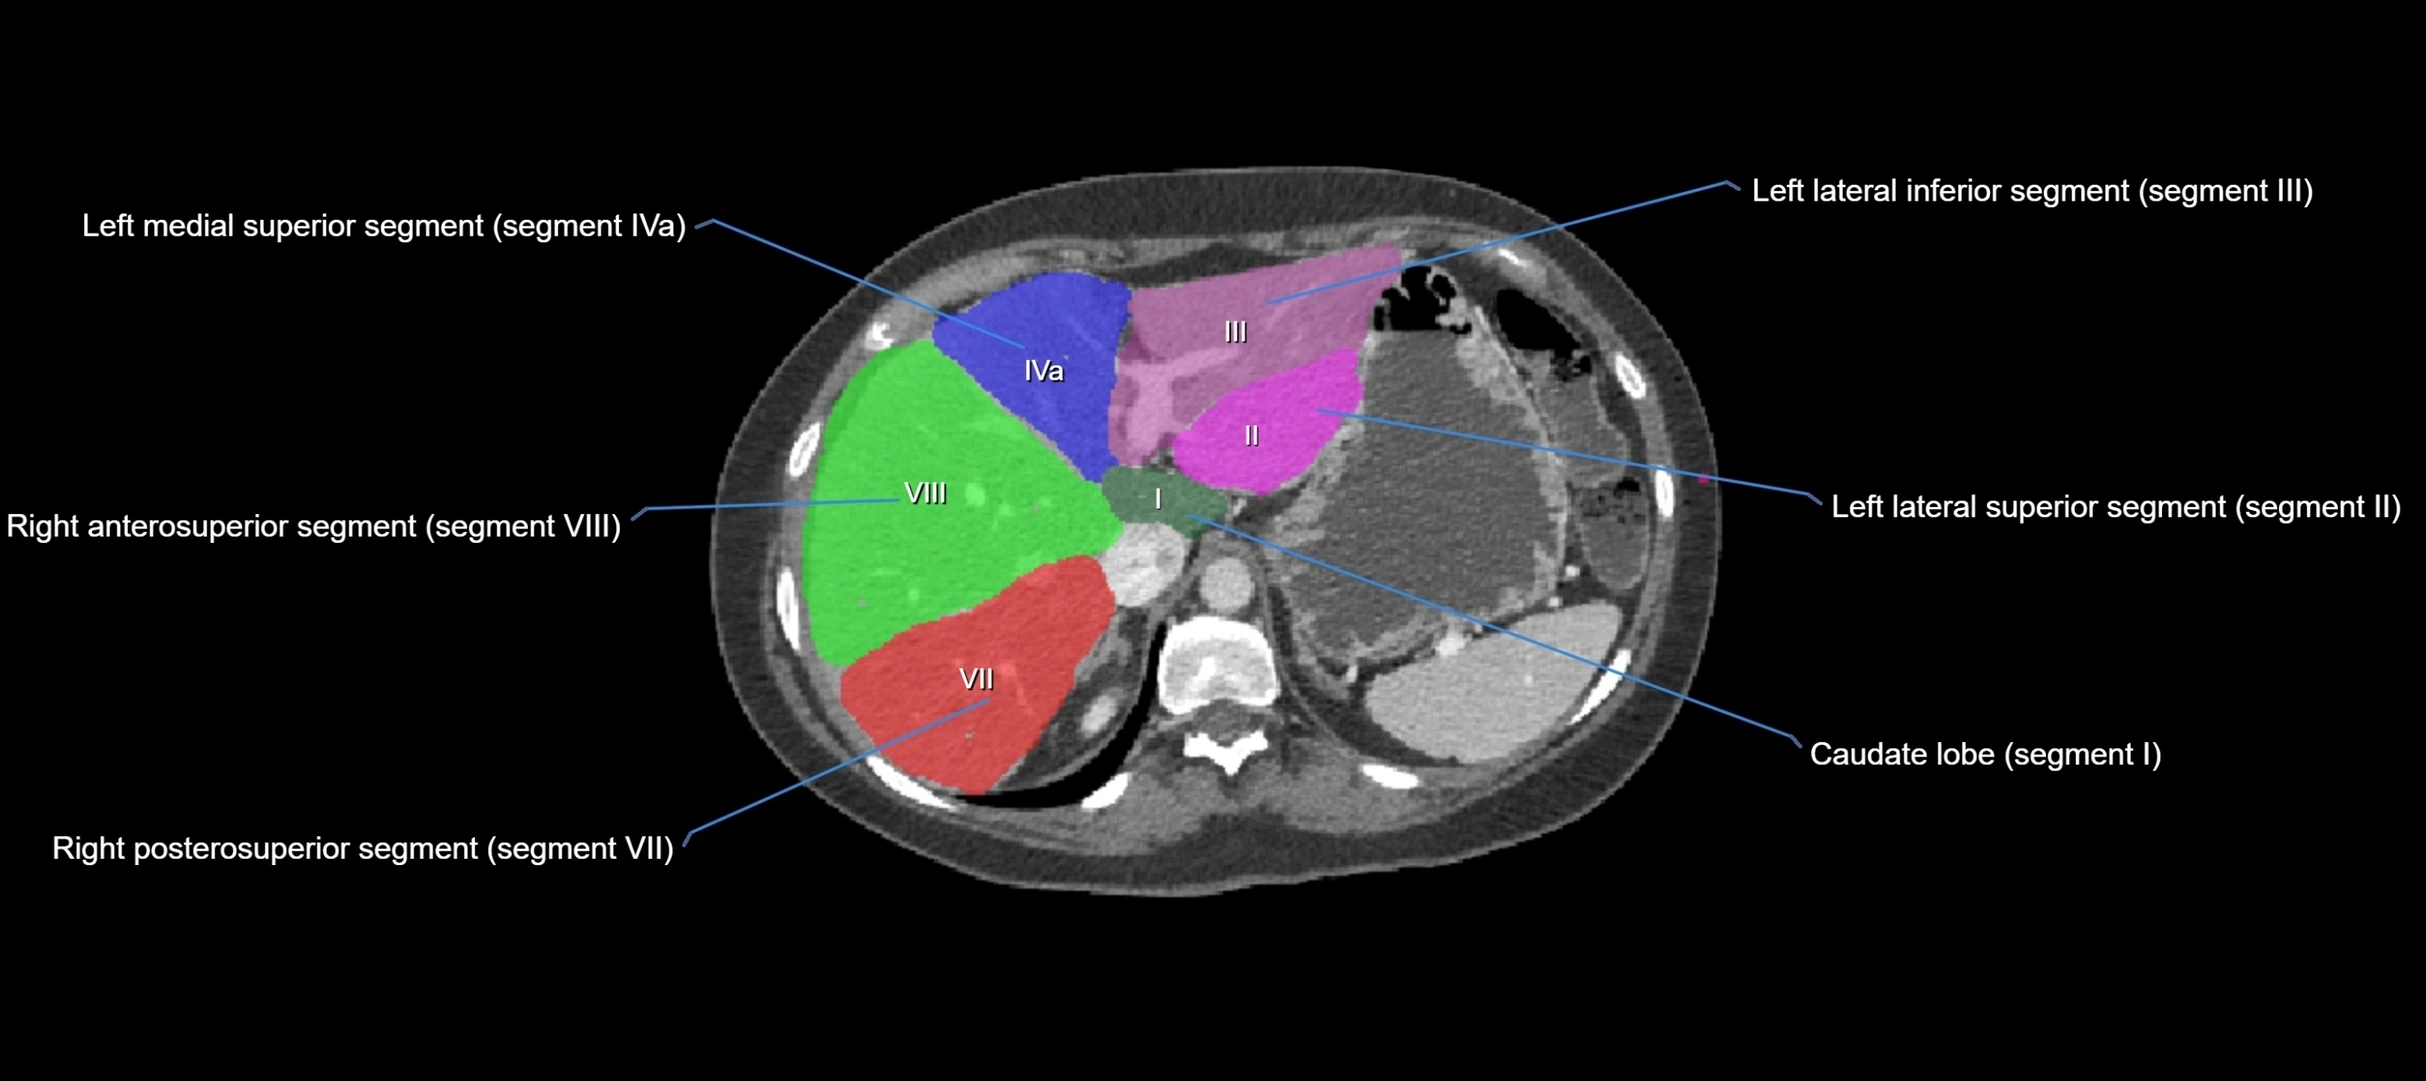

CT Image

image